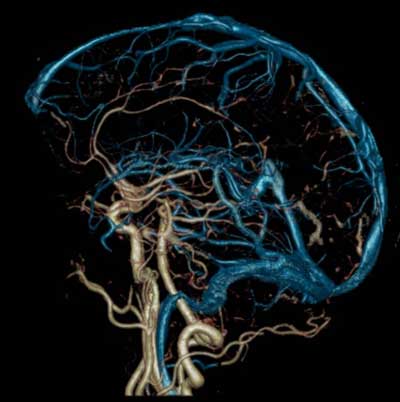

Снижение кровообращения в головном мозге — опасное для жизни явление. Анатомия человека такова, что функцию компенсации недостаточного кровотока выполняет расположенное в субарахноидальном пространстве на основании мозга артериальное кольцо (виллизиев круг).

Сосуды мозга соединяются между собой (анастомозируют) на основании ГМ. Образуют бассейн виллизиева круга такие сосуды:

- Передняя мозговая артерия: начальный сегмент (a. cerebri anterior).

- Передняя соединительная артерия (a. communicans anterior).

- Внутренняя сонная артерия: супраклиновидный сегмент (a. carotis interna).

- Задняя соединительная артерия (a. communicans posterior).

- Задняя мозговая артерия: начальный сегмент (a. cerebri posterior).

В своей работе Виллизий Томас описывает анастомоз в виде семиугольника — гептагона Виллизия. Но проведя исследования, М. А. Тихомиров выявил, что форма кольца девятиугольная. Связь между сосудами ГМ централизуется в виллизиевом круге.